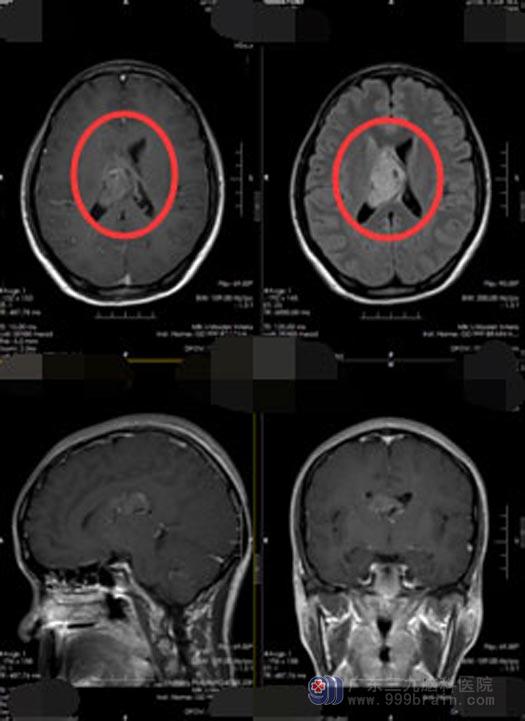

广东三九脑科医院行头颅MR检查提示:右侧侧脑室占位性病变,考虑为中枢神经细胞瘤可能性大。中枢神经细胞瘤对放疗敏感,直接手术风险极大,为减少手术风险,经多学科讨论后,决定先放疗再手术。

一周的放疗结束后,由医院副院长、神经外五科主任鲁明主刀行“右侧侧脑室神经细胞肿瘤切除术”,术中见肿瘤呈灰白色,质软,血供丰富,显微镜下将肿瘤分块全部切除。术后病理提示:不典型中枢神经细胞瘤,WHO II级。术后已解除病症,林小姐恢复良好,已经出院。